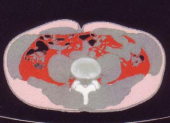

内臓脂肪が実際どの程度なのかを調べるために腹部CTスキャンを撮ってもらいました。添付の画像が結果です。上側がお腹側、下側が背中です。赤い部分が内臓脂肪です。ピンクは皮下脂肪です。背中の横側がちょっと付いています。しっかりつまめます。(^^;)

で、内臓脂肪の断面積は61.1平方cmでした。100未満がよいとされていて、61という結果が出たということで、ほっとしています。

実は、日々体組成計で測っている「内臓脂肪レベル」というは内臓脂肪の断面積の推定値と相関があって、例えば内臓脂肪レベルが11なら、内臓脂肪の断面積は110平方cmというように、内臓脂肪レベル×10が断面積に近い数値になるとのことです。

私のこのところの内臓脂肪レベルは6ですので、断面積が61というのは非常に妥当な感じがします。

先生がおっしゃるには、61という数字は決して悪くないので、これを維持してください、ということ、ある程度内臓脂肪も必要なので、極端に落とすのはよくない、とのことでした。

あと、皮下脂肪は67.9平方cmあって、特に背中の脂肪はもうちょっと落としてもよいとのことでした。